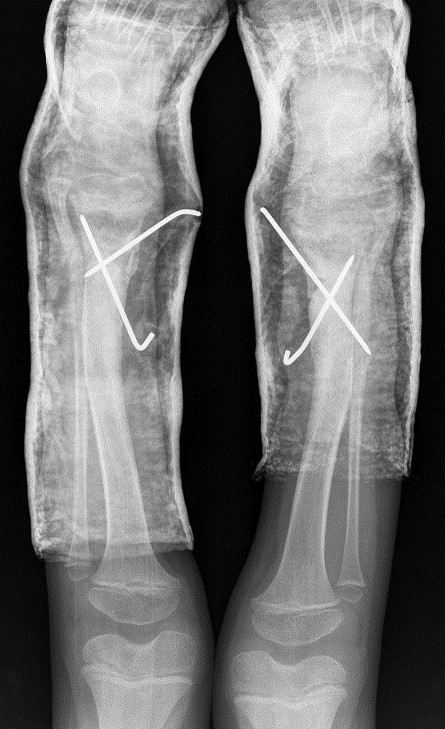

The X-ray showed a bowing of distal tibia, bilaterally, producing a varus deformity of 53 degrees (Fig. 2).